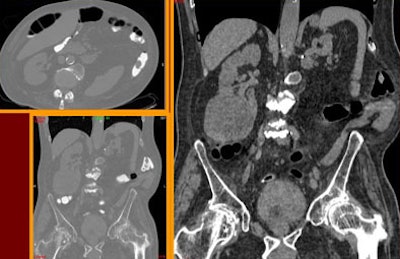

![]() |

| Above and below: Despite suboptimal distension, VC detected two significant polypoid lesions in the sigmoid colon of a 61-year-old paraplegic with fecal occult blood, following unsuccessful colonoscopy. The patient's parents had both died of colon cancer. Digital subtraction was used to detect the fluid-submerged polyps. |

| In a 72-year-old screening patient with severe diverticular disease, the colonoscope had stopped at the sigmoid colon. VC results showed the colon to be free of disease, but detected a very large extracolonic mass, diagnosed as a peritoneal liposarcoma. |